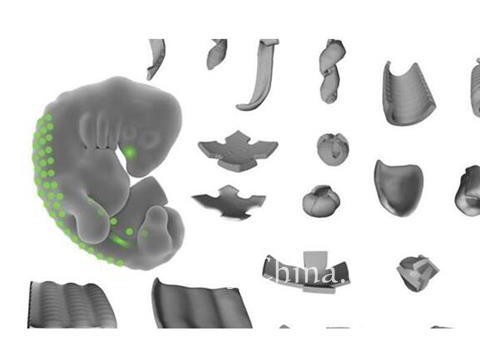

- 创新3D打印解剖模型软件,Stratasys持续推动个性化医疗发展

- Materialise软件+Stratasys硬件,超乎寻常的通用型医用3D打印系统?